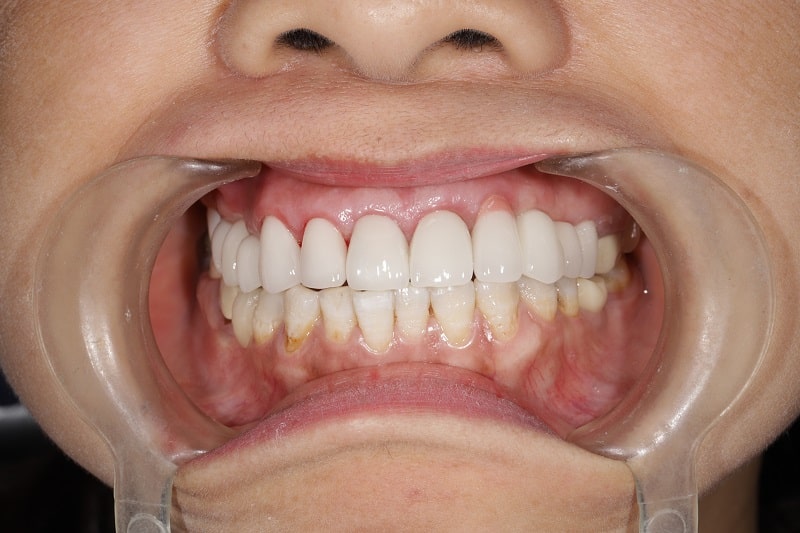

Hình ảnh bệnh nhân trám răng tại nha khoa

Một số trường hợp dễ gặp như: răng bị sứt mẻ do va chạm mạnh, răng bị ngắn bẩm sinh, răng bị thưa do quá trình mài mòn của acid, răng bị sâu và tổn thương tủy,…